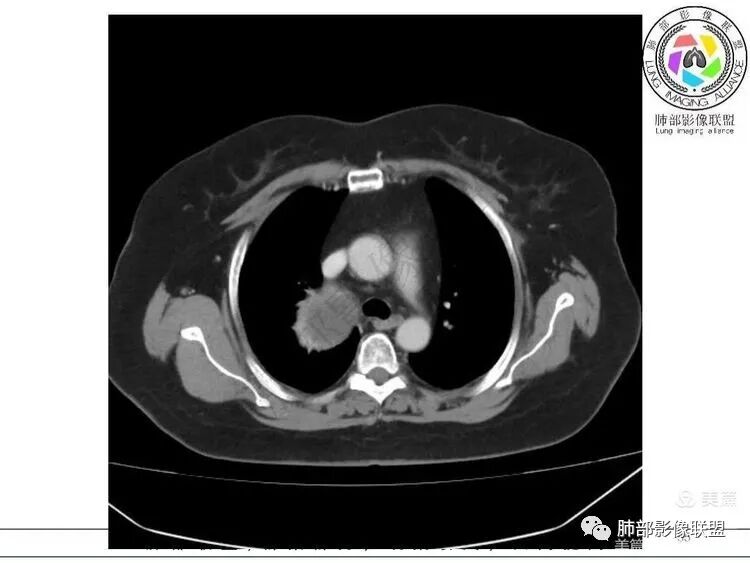

大雄:定位: 纵隔(往左推移气管 往前推移腔静脉 往下推移肺尖胸膜)定性: 良性(边缘光滑,与周围结构境界清晰,无侵袭性生长特点)特征:增强可见AB区(富细胞区与粘液区),延迟强化明显。考虑:神经鞘瘤 ,鉴别:SFTKing:纵隔偏良性肿瘤,与甲状腺无关。首先考虑神经鞘,其他如副节,SFT,巨淋巴待鉴别。飞鹰行动:右侧上胸腔近纵膈类圆形软组织占位,边界清晰光滑,内见囊变,增强渐进性强化,考虑来源纵膈的病变,神经鞘瘤可能,鉴别孤立性纤维瘤。小兜:右上纵隔椭圆形占位,胸膜掀起,肺组织受压,气管受压移位,考虑来源于纵隔,边缘光滑,增强扫描渐进性不均匀强化,内见大片无强化区,考虑为神经鞘瘤可能,鉴别SFT。陈学君:后纵隔占位,多发囊变,渐进強化,考虑鞘瘤,鉴别SFT红星:右上胸廓入口类圆形肿块,肺瘤界面清晰,肺支气管及血管受压,强化不均,片状楔形坏死,考虑来源纵隔占位,神经鞘瘤。鉴别STF、肉瘤?宇宙:右上后纵隔旁椭圆形肿块,边缘光整,向上突入颈根部,肺组织、血管及气管受压移位,密度不均匀,不均匀渐进强化,囊变,考虑神经鞘瘤,鉴别SFT

Kery Wang:

右侧上胸腔近纵膈类圆形软组织占位,边界清晰光滑,考虑来源纵膈的病变,神经源性可能,鉴别孤立性纤维瘤。医然为伱つ:有AB区,首先考虑鞘瘤,鉴别SFT

1. 右上胸廓入口区类椭圆形块影,边界清楚光整,纵向“嵌顿”于颈根部及上纵隔,向上推移右锁骨下动静脉,向外下方推移上肺胸膜及肺组织(肺血管、支气管),向前推移上腔静脉,界限清楚。

2. 块影不均匀轻度强化,可见较均匀实性区及液性密度区,未见积气、囊壁样结构、钙化或脂肪密度。可疑部分肋间动脉分支进入。

3.块影相邻椎骨及肋骨明确推压或骨质吸收破坏,未见椎管内结节或椎间孔扩大。

4.双肺门及纵隔未见肿大淋巴结。